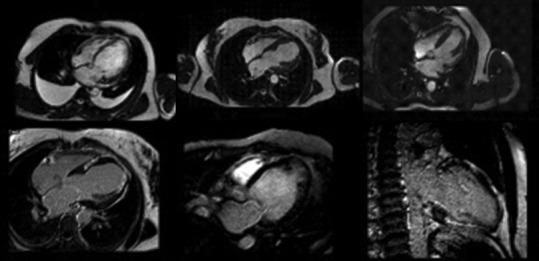

Cardiovascular diseases (CVDs) remain the leading cause of morbidity and mortality worldwide, and traditional preventive measures focus on lifestyle modifications, pharmacologic interventions, and risk stratification. Recently, imaging has emerged as an interesting tool in cardiovascular prevention. This review explores the role of various imaging modalities in early detection, risk assessment, and disease monitoring. Noninvasive techniques such as carotid ultrasound, arterial stiffness assessment, echocardiography, and coronary artery calcium scoring enable the identification of subclinical atherosclerosis and ventricular dysfunction, providing insights that complement conventional risk factors. Coronary computed tomography angiography and cardiac magnetic resonance offer high-resolution visualization of vascular and myocardial pathology, contributing to refined risk stratification. Furthermore, emerging markers such as epicardial adipose tissue and hepatic steatosis are gaining recognition as potential predictors of cardiovascular risk. Advancements in artificial intelligence (AI) are revolutionizing cardiovascular imaging by enhancing image interpretation, automating risk prediction, and facilitating personalized medicine. Future research should focus on optimizing the integration of imaging into clinical workflows, improving risk prediction models, and exploring AI-driven innovations. By exploiting imaging technologies, clinicians could enhance primary and secondary prevention strategies, ultimately reducing the global burden of CVDs.

心血管疾病(CVDs)仍然是全球发病和死亡的主要原因,传统的预防措施集中在生活方式改变、药物干预和风险分层上。最近,影像学已成为心血管预防领域一项引人关注的工具。本综述探讨了各种影像学检查方法在早期检测、风险评估和疾病监测中的作用。诸如颈动脉超声、动脉僵硬度评估、超声心动图和冠状动脉钙化积分等非侵入性技术能够识别亚临床动脉粥样硬化和心室功能障碍,提供补充传统危险因素的见解。冠状动脉计算机断层扫描血管造影和心脏磁共振成像能够对血管和心肌病变进行高分辨率可视化,有助于更精确的风险分层。此外,诸如心外膜脂肪组织和肝脂肪变性等新兴标志物正逐渐被认可为心血管风险的潜在预测指标。人工智能(AI)的进步正在通过增强图像解读、自动化风险预测和推动个性化医疗来彻底改变心血管成像。未来的研究应聚焦于优化影像学在临床工作流程中的整合、改进风险预测模型以及探索人工智能驱动的创新。通过利用成像技术,临床医生可以加强一级和二级预防策略,最终减轻全球心血管疾病负担。